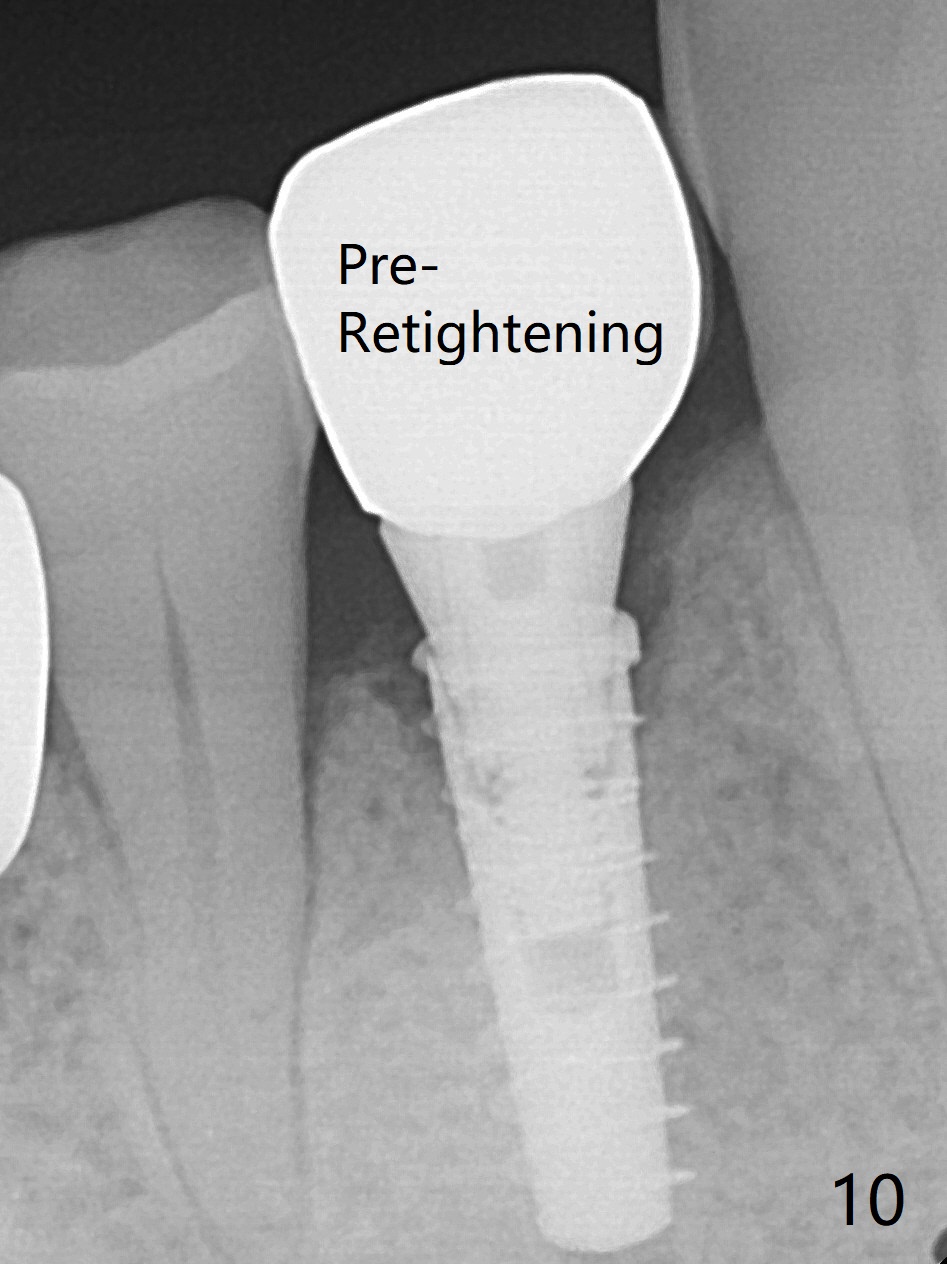

In fact the mesiodistal space of the site of #28 is within normal limit. The buccal plate atrophy is striking (Fig.1) with a fistula (^, associated with underlying residual root tip). When the flaps are raised, the ridge is triangular with the lingual plate (Fig.2 *) higher than the buccal one. Because of the slope, the multiple-drill approach is adopted in stead of single-drill one, because the marking bur is wobbling after 1.6 mm osteotomy at 13 mm (Fig.3). After placement of a 4x11 mm implant, a 4.5x4(2) mm abutment is inserted (Fig.4). The abutment and the implant act as a mesh (framework) so that bone graft and collagen membrane can be laid upon them buccolingually. When the flaps are sutured, there is less tension than that without the abutment. Furthermore, the buccal tissue volume seems to be increased (Fig.5 (<: fistula, which should heal soon), as compared to Fig.1). Tale photos to show effectiveness of the simultaneous GBR and disappearance of the fistula. Three months postop (Fig.6,7 (incomplete abutment seating)), the implant is loaded for intrusion of the opposing supraerupted tooth. The patient returns with chief complaint of food impaction between #27 and 28 three years 7 months post cementation; there is an open contact. Before pick up impression the distal convex surface of #27 is trimmed. The repaired crown has tight proximal contacts before (Fig.9,10) and after (Fig.11) retightening and cementation.